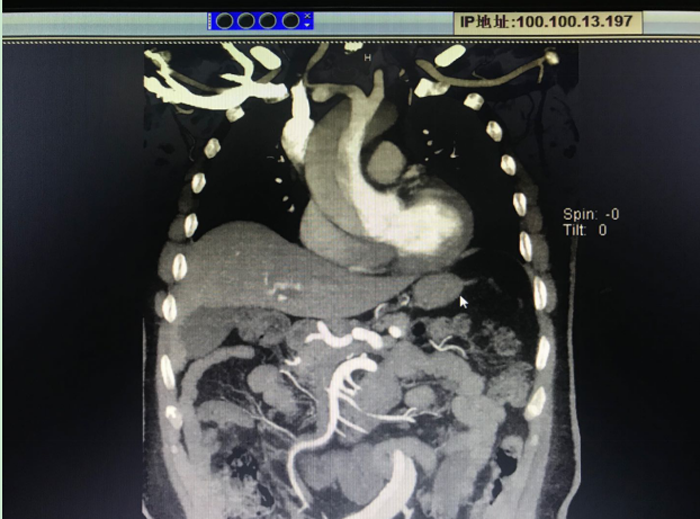

患者術(shù)前CT

患者男,48歲,因持續(xù)胸背部疼痛不適1小時來我院急診就診,急診行主動脈CTA檢查,確診為主動脈夾層(Stanford A型)。醫(yī)生告知患者家屬,患者病情危重,需要盡快手術(shù)治療才有生的希望。但棗莊地區(qū)從未開展過這種“超級手術(shù)”,以往這種情況都只能轉(zhuǎn)到濟南、北京、上海等大醫(yī)院手術(shù),并且不少患者在轉(zhuǎn)運過程中因夾層破裂導(dǎo)致死亡?;颊卟∏槲V兀覍贁M轉(zhuǎn)上級醫(yī)院行手術(shù)治療。但由于患者動脈夾層累及右冠狀動脈,右冠狀動脈根部撕裂,心包大量積血,患者生命體征不平穩(wěn)血壓降至58/30mmHg,不宜轉(zhuǎn)運。為此,全院高度重視,隨即聯(lián)系山東大學(xué)齊魯醫(yī)院龐新焱教授來我院協(xié)助進行升主動脈+主動脈弓人工血管置換+降主動脈象鼻支架置入術(shù)。